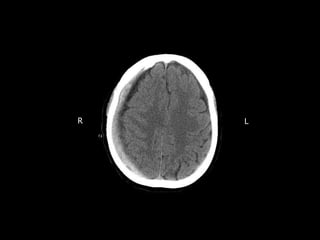

Case #3  Ms.JH is a 66 y/o female who slipped down the stairs yesterday and hit the back of her head.  She presents with  Generalized left sided weakness  Light headache  A non-contrast CT scan of her brain is performed

• 66.

• 67.

Your analysis  Whatare your findings?  What is your impression?  What would be your top diagnosis?  Is this pathology acute, subacute, or chronic

• 68.

Case #3 -Answer  Mrs. JH had a large right- sided subdural hematoma  The hematoma is acute  This was caused by rupture of bridging veins when she hit her head  A craniotomy was performed and the bleed was drained